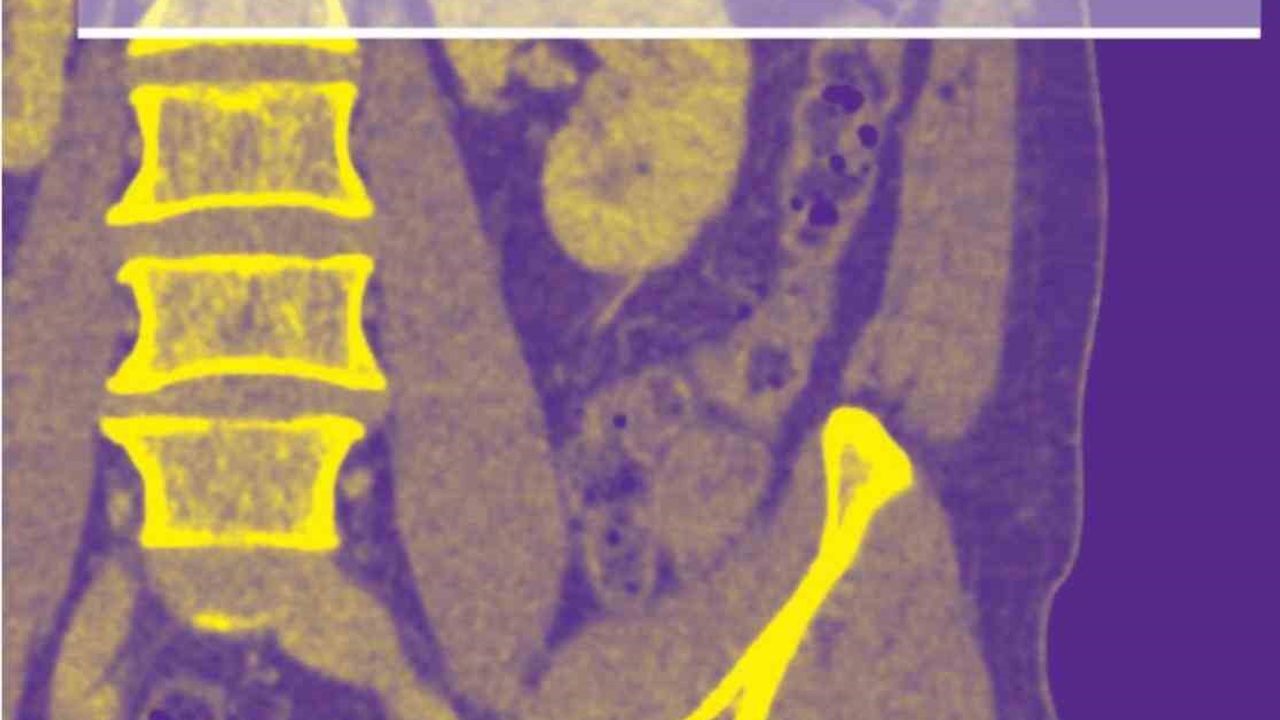

Bir dönem Denizli Tekden Hastanesinde de çalışan ve çalışmalarına ABD'de devam Dr. Nevzat Karabulut ve ekibinin yaptığı, British Journal of Radiology dergisinde yayımlanan 'Diagnostic performance of contrast-enhanced and unenhanced combined pulmonary artery MRI and magnetic resonance venography techniques in the diagnosis of venous thromboembolism' başlıklı araştırmada manyetik rezonans (MR) yöntemi kullanılarak hem akciğer damarlarının hem de pıhtının kaynağı olan bacak toplardamarlarının aynı anda, tek bir incelemede değerlendirilebileceği gösterildi. Toplam 44 hastanın incelendiği çalışmada elde edilen sonuçlar oldukça dikkat çekti.

Kontrastlı MR yöntemi, hastaların tamamında akciğer embolisini doğru şekilde tespit ederken; kontrastsız MR yöntemi de yüksek doğruluk oranına ulaştı ve önemli ölçüde güvenilir sonuçlar verdi. Bu bulgular, radyasyon içermeyen MR yönteminin pıhtı hastalığını saptamada güçlü bir alternatif olduğunu ortaya koydu. Özellikle Radyasyon riskinin daha önemli olduğugenç hastalarda ve gebelerde MR'ın güvenli ve etkili bir seçenek olabileceği vurgulandı.

Uluslararası literatürde yankı uyandıran çalışma hakkında bilgi veren Dr. Nevzat Karabulut, 'Akciğer embolisi, genellikle bacak damarlarındaki pıhtının dolaşımla akciğer damarını tıkaması sonucu oluşan ve zamanında fark edilmediğinde hayati tehlike oluşturabilen acil bir tıbbi durumdur. Bugün bu hastalıkları teşhis etmek için en sık Radyasyon içeren ilaçlı bilgisayarlı tomografi (BT) anjiyografisi kullanılıyor. Ancak Radyasyon ve kullanılan kontrastlı madde özellikle hamileler, genç hastalar ve kontrast maddeye alerjisi olan kişiler için risk oluşturabilir. Bu nedenle doktorlar radyasyon içermeyen ve daha güvenli alternatif yöntemler üzerinde çalışmaktadır. Ekibimle birlikte yapılan bilimsel çalışmanın büyük uluslararası araştırmalarda kaynak olarak gösterilmesi, o çalışmanın ne kadar değerli ve etkili olduğunu gösterir. Bu durum, yapılan araştırmanın sadece yayımlandığı dönemde değil, uzun vadede de bilim dünyasına katkı sağladığını ortaya koyar' dedi.